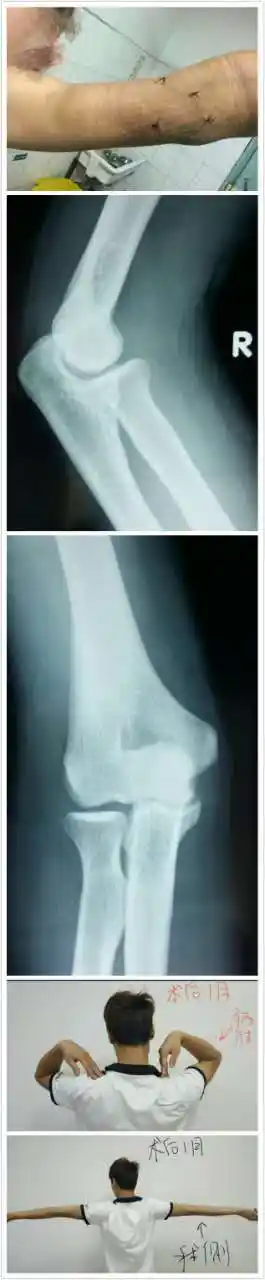

关节镜下治疗肘关节游离体